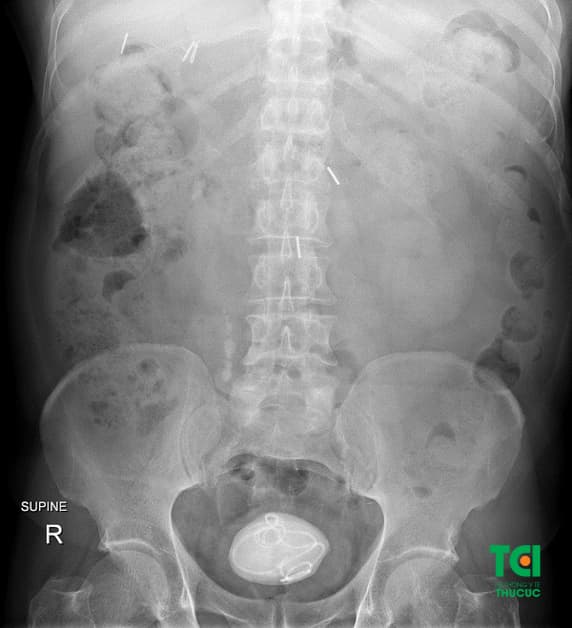

1.2 Một số hình ảnh sỏi bàng quang trong hệ tiết niệu

Sỏi với kích thước rất lớn nằm trong bàng quang bệnh nhân

Qua những hình ảnh thực tế về tình trạng sỏi bàng quang của nhiều bệnh nhân, có thể thấy hầu hết người bệnh đến viện khi các viên sỏi đã đạt kích thước lớn, gây ra những triệu chứng ảnh hưởng đến cuộc sống sinh hoạt và làm việc của người bệnh.